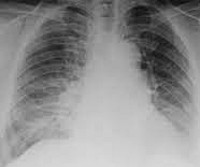

Методы лучевой диагностики имеют вспомогательное значение. Специфичных для биссиноза рентгенологических признаков не существует. Рентгенография и КТ органов грудной клетки помогают обнаружить наличие бронхоэктазов, эмфиземы и других лёгочных осложнений. Определение общего и специфического IgЕ, прик-тесты позволяют выявить сенсибилизацию к пыльце, продуктам питания, бытовым и эпидермальным аллергенам и отличить биссиноз от бронхиальной астмы. Степень поражения правых отделов сердца определяется с помощью эхокардиографии.